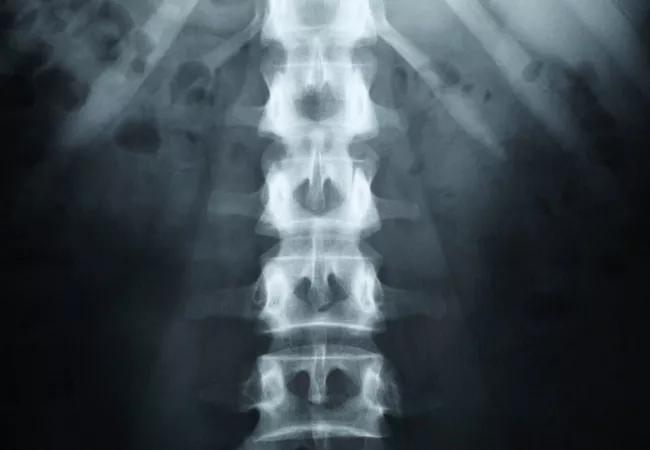

Over time, chemotherapy and radiation therapy can lead to severe neuropathic pain for cancer patients. Other sources of cancer pain come from bone metastases, nerve and spinal cord compression, as well as pressure on the organs. Cleveland Clinic Pain Management specialists work in collaboration with oncology physicians and palliative care specialists to help cancer patients control pain when other remedies fail.

In recent years, another therapy that is becoming more established as an alternative or additional technique to help relieve cancer pain is the OsteoCool system, notes Dr. Costandi. This technique uses bipolar water-cooled radiofrequency ablation to treat spinal pain that is secondary to metastatic vertebral tumors. This outpatient procedure involves a probe being inserted at the vertebral level. It is best for patients who have one to three lesions that have been localized to the spine, are not candidates for radiotherapy and do not have a neurological deficit – or spinal cord compression.

Dorsal root ganglion (DRG) stimulation is a neuromodulation therapy, similar to traditional spinal cord stimulation (SCS) that is being applied more and more to relieve cancer pain. Rather than placing electrodes over the posterior aspect of the spinal cord as in SCS, leads are implanted on the dorsal root ganglion, a cluster of neurons in the posterior root of spinal nerves, which modulate all bodily sensations. DRG stimulation is a particularly effective therapeutic approach for patients with chronic intractable neuropathic pain.

DRG stimulation offers a highly-directed stimulation field, which can focus stimulation to the painful area. The FDA has approved DRG stimulation for lower extremity CRPS, which could include neuropathic pain conditions and chronic pain following surgeries (like thoracotomy) commonly performed in cancer patients.